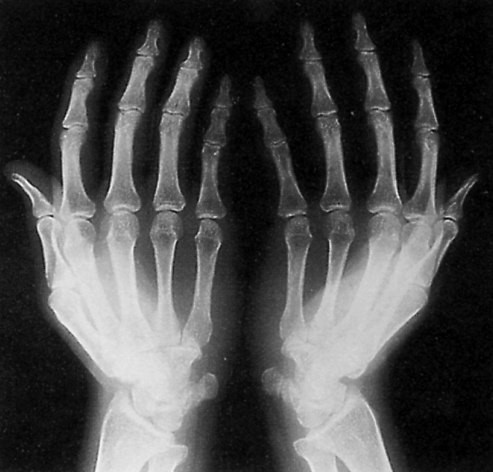

Zda se jedná o úplnou nebo neúplnou rupturu anebo jen natažení (přetažení, distenzi) musí být prokázáno dalšími vyšetřovacími metodami sonografie (přednostně – umožňuje vyšetření při pohybu), ideálně magnetické rezonance. (viz.obrazky)

Přerušení poutek A2, A3, vznik šlachové tětivy